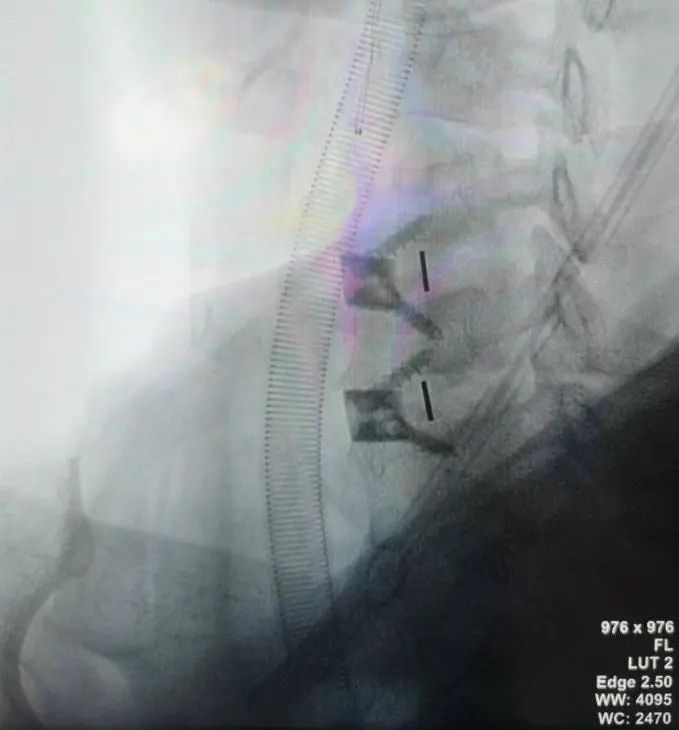

4.效果展示